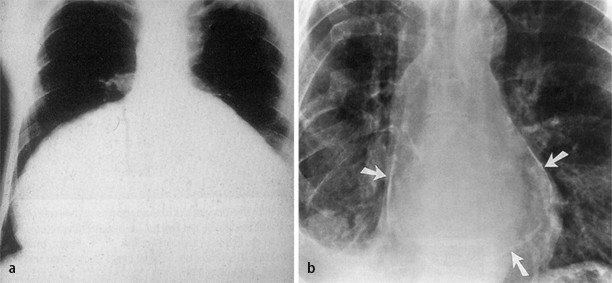

The heart silhouette was enlarged in 23 and small in only 4. Perikarderkrankungen aus kardiologischer und kardiochirurgischer Sicht. Constrictive pericarditis is long-term or chronic inflammation of the pericardium.

The true population prevalence is unknown but amongst those with viral pericarditis it has been estimated to occur in less than 05 of cases. They should be essential in everyday clinical decision making. In 12 tuberculosis and rheumatism were found to be the etiologic factorsX-rays showed calcium deposits in 69.